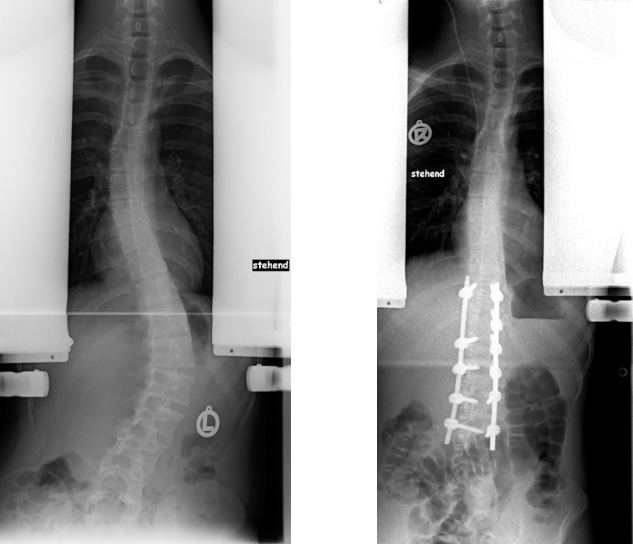

Wachstumslenkung (Vertebral Body Tethering - VBT)

Bei der VBT Methode, auch auch Anterior tethering genannt wird, wird operativ von vorne-seitlich an der Wirbelsäule ein sehr festes Band angebracht. Es soll das Wachstum auf der Konvexseite gebremst werden, damit die kürzere konkave Seite nachwachsen kann. Die Korrektur erfolgt also nicht bei der Operation, sondern erst allmählich während des Wachstums.

Gedacht ist es für Patientinnen und Patienten mir sehr flexibler Krümmung, die jedoch schon so weit fortgeschritten ist, dass man davon ausgeht, dass eine Korsettbehandlung allein nicht zum Erfolgt führt. Da noch eine Restbeweglichkeit erhalten bleibt, wird es auch als "Begradigung ohne Versteifung" propagiert und zunehmend auch bei ausgewachsenen Patientinnen und Patienten eingesetzt. Für diese ist es aber eigentlich nicht vorgesehen.

VBT-Methode

Aktuell wird es empfohlen für Krümmungen zwischen 35 und 70 Grad, die sich spontan um 50 Prozent und mindestens unter 30 Grad korrigieren lassen. Der optimale Zeitpunkt ist zu Beginn der Pubertät, wenn noch genügend Wachstumspotential vorhanden ist. Um dies zu bestimmen, sollte die Hand geröntgt werden. Setzt man das System zu spät ein und korrigiert vornehmlich nur über die Seile, dann ist die Gefahr groß, dass diese reißen. Setzt man das System zu früh ein, besteht die Gefahr der Überkorrektur, weil das Restwachstum schwer vorhersehbar ist.

Wie lange das funktioniert, ob die Wirbelsäule dann irgendwann doch versteift oder das Band ausreißt und wie es dann weitergeht, ist noch nicht abschließend geklärt, weil es keine Studien gibt, die die Patienten länger als fünf Jahre beobachtet haben. Für einige Patienten, die kurz vor Beginn oder am Anfang der Pubertät schon eine starke Krümmung haben, könnte dieses System durchaus auch dauerhaft von Vorteil sein. Es sollte jedoch nicht grundsätzlich als Ersatz für eine Korsettbehandlung gesehen werden.